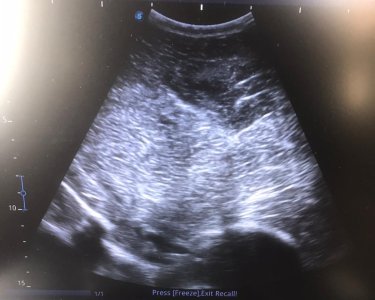

I don’t have undoctored images of this but this is the most random equine diagnostic image I’ve got I think. Anyone like to guess the imaging modality and what the arrow is pointing at?

Yup. Where the yellow line is it should be a natural curve. Instead there is a step where the pelvis has broken and displaced. It's really not an obvious one unless you know you were looking at a pelvis - which hopefully none of you lot ever have to!

We're at a disadvantage here because if you take an xray or do an ultrasound, presumably you know which part of the body you're aiming at. :D